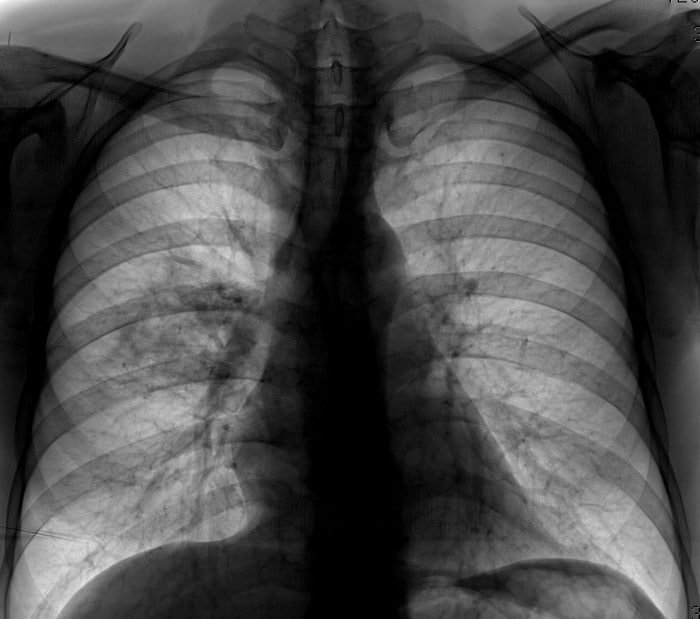

Значит черное легкое на рентгене это плохо уже...хотя описание в норме

это НОРМА)

ну или вот)

о ужас, черные легкие норма)

любая чернота норма в данном случае)

а полностью серые — не норма)

бывает еще в обратную сторону. Вот так)

Но это редкая история

так выглядит чаще и это норм